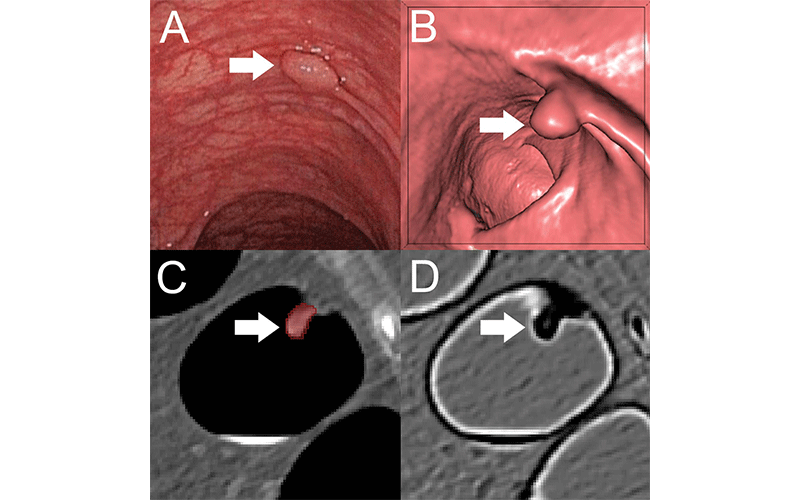

A machine learning (ML) algorithm helps accurately differentiate benign and premalignant colorectal polyps on CT colonography scans, according to a study in Radiology.

During the last two decades, CT colonography emerged as a noninvasive alternative to colonoscopy in screening for colorectal cancer. It is comparable to colonoscopy in detecting most polyps and is effective at visualizing portions of the colon that in cases of complex anatomical conditions cannot always be evaluated by colonoscopy. However, CT colonography does not enable a definite differentiation between benign and premalignant polyps, which is crucial for individual risk stratification and therapy guidance.

The researchers developed a ML algorithm to predict the character of the individual polyps based on quantitative image features extracted through radiomics. They applied the noninvasive, radiomics-based ML method on CT colonography images from a group of asymptomatic patients at average risk of colorectal cancer. The algorithm was trained on a set of more than 100 colorectal polyps in 63 patients and then tested on a set of 77 polyps in 59 patients.

In the test set, the ML approach enabled noninvasive differentiation of benign and premalignant CT colonography-detected colorectal polyps, with a sensitivity of 82%, and specificity of 85%. The area under the curve (AUC) was excellent.

“These results serve as proof-of-concept that machine learning-based image analysis allows the noninvasive differentiation of benign and premalignant colorectal polyps in CT colonography data sets,” said study lead author Sergio Grosu, MD, radiologist from University Hospital, Ludwig Maximilian University of Munich, in Munich, Germany. “The AUC of 0.91 indicates that this method works well.”